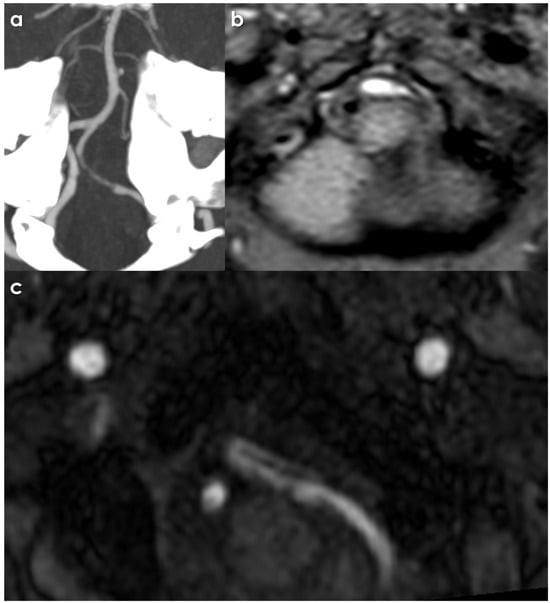

An example of CTA and MTI signs of intracranial VAD is illustrated in Figure 1.

Figure 1.

Intracranial left VAD. The CTA panel (a) shows a long-tapered stenosis, corresponding with the flow in the true lumen, as outlined by the presence of a mural hematoma and hyperintense T1 Dixon MRI panel (b) with an intimal flap (panel (c), MRA source image).